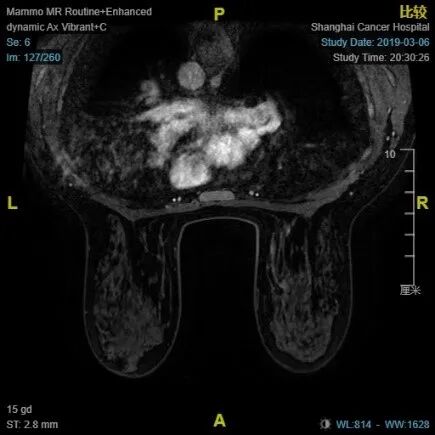

•  2018.11.5我院乳腺MRI:右乳内上肿块,符合恶性肿瘤表现,BI-RADS 6。

4疗程治疗后评估:CR

4疗程后MRI:右乳癌治疗后较前好转,BI-RADS:6。 右腋下小淋巴结同前